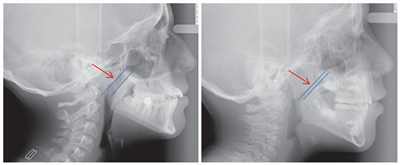

左为正常面容,右为腺样体面容

腺样体肥大阻塞后鼻道,患儿不得不张口呼吸,而且在夜间尤为明显。长时间张口呼吸导致颌面发育异常,上唇上翘变短、开唇露齿、门齿外铲、嘴唇外翻、下颌后缩、甚至目光呆滞。